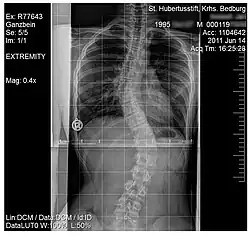

Scoliosis

.jpg)

Scoliosis, is a medical condition where a person's spine has several irregular curves that are located between the neck and the pelvis.[8] Symptoms of scoliosis in mild cases usually exhibit abnormal posture, back pain, tingling or numbness in the legs and in worse cases can exhibit breathing problems, fatigue, permanent deformities and in rare cases heart problems.[8]

Although the cause of scoliosis can sometimes remain unknown (idiopathic scoliosis) there is treatment available that targets at strengthening the back muscles, for milder cases usually do not require medical attention, more severe cases require either muscle strengthening exercises aimed at the back muscles and even special back braces or surgery can be recommended if the case is extreme.[8] Studies have shown that treatment with a special back brace among children ranging from 10–16 years can be successful and using this method of muscle training scoliosis can be cured with non-surgical treatment.[17]